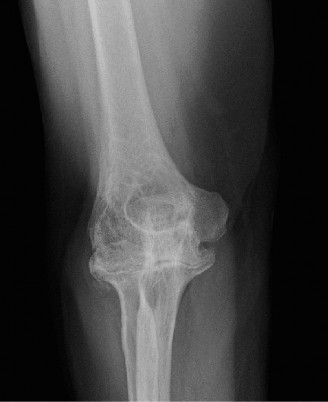

Understand common complications associated with performing surgery for scapulothoracic bursitis? CASE 33 A 42-year-old female presents to the office for follow up after sustaining a minimally displaced radial head fracture 3 months prior. She states she was initially treated in long-arm splint by the ER and did not follow up with an orthopaedic surgeon until now. Per her report, she removed the splint 4 weeks after the injury, but did not move her elbow due to pain. She now has no pain but is unable to reach that hand to her face or head. The remaining history is significant for previous ulnar nerve surgery for which she is unable to provide details. On physical examination, her upper extremity is normal except for limited flexion/extension, measured to be 80 to 50 degrees by goniometer. In addition, she has a well-healed surgical incision about the medial elbow, consistent with a previous surgery on her ulnar nerve. Her images are shown (Figs. 2–82 to 2–84).

Figure 2–82

Figure 2–83

Figure 2–84

What is the diagnosis?

- Early post-traumatic intrinsic joint contracture

- Late post-traumatic extrinsic joint contracture

- Late combined post-traumatic joint contracture

- Early combined post-traumatic joint contracture

Discussion

The correct answer is (A). Classification of post-traumatic elbow stiffness allows for better understanding of the disease and allows the clinician to treat the underlying cause of the joint contracture. Intrinsic causes include: any problem within the joint such as incongruency, loose bodies, or severe osteoarthritis. Extrinsic causes include capsular tightness, muscle contracture, heterotopic ossification, and skin contractures. Early is defined as within 6 months of the injury while late is considered to be greater than 6 months after the injury. Patients that present in the early time frame have a significantly better chance at having a good result both from nonoperative and operative treatment.